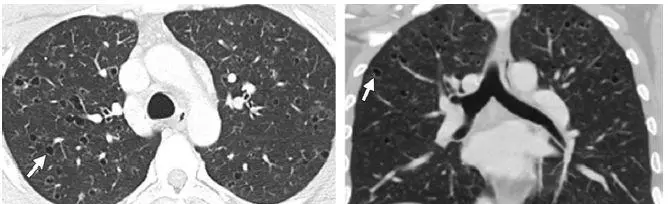

早期疾病薄层断层扫描(CT)可显示1–10mm的小叶中心结节或者空洞(图1)。随着病情的发展,囊性病变逐渐取代结节,表现为厚或薄壁囊腔,形态多不规则(图2)。结节和囊性病变通常累及双肺上中野,肺尖和肺底以及肋膈角常不受累。约25%的患者由于胸膜下囊腔破裂导致自发性气胸,累及双侧并且可以反复发作,这是本病的首发症状(图3)。终末期疾病的特点是肺过度充气以及广泛的囊腔,形成终末期肺气肿(图4)。薄层CT具有特征性人口统计学分布特点及临床表现,是PLCH临床诊断的重要依据,从而避免肺活检。在儿童中,薄层CT表现与成人相似,但更病变更广泛(图5),并且与未发现与吸烟有关的病灶。

图2 31岁男性PLCH患者。薄层CT横轴位(a)和冠状位(b)显示双肺上叶不规则状囊腔,囊壁厚度及囊的大小多变(箭头),双肺基底未受累。